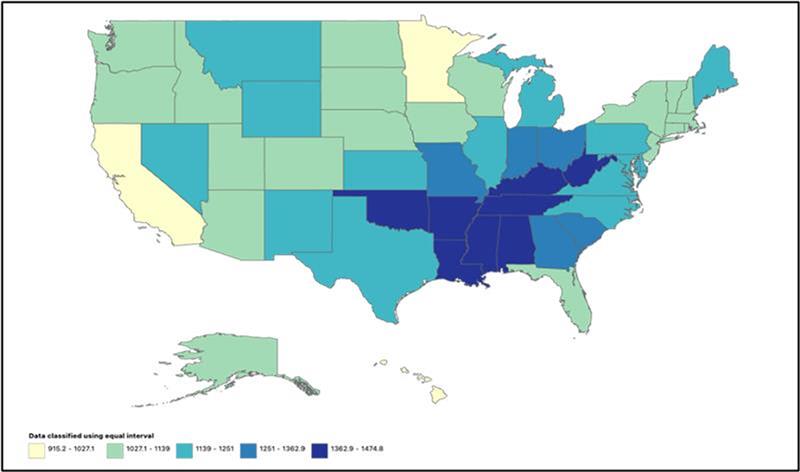

Temporal Trends and Disparities Related to Intrahepatic Cholangiocarcinoma Among Adults Living in the United States: A 1999 to 2020 Retrospective Analysis

Introduction: Intrahepatic cholangiocarcinoma (IHCC), the second leading cause of liver-related mortality, carries a poor prognosis. Although its incidence has risen...Read More